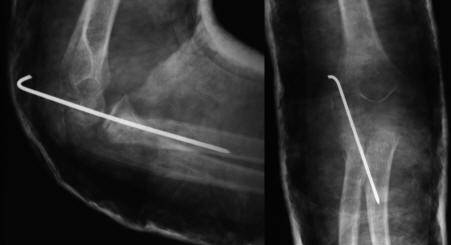

8 岁女孩桡骨颈骨折。

接近 90 度(>30度)成角的桡骨颈骨折,仍首先尝试 Patterson 与以色列法等闭合复位方法.

难推动倒斜下的桡骨颈,闭合复位失败,2.0 克氏针扁头经皮撬拨骨折断端,克氏针钝头复位骨折。

取出复克氏针,已经比较稳定,但侧片看见桡骨近端仍有轻微向后、外移位趋势,存在潜在不稳定。

1.5 克氏针固定,避免向后外移位趋势(术后正、侧位X线片及置针的肘部外观)